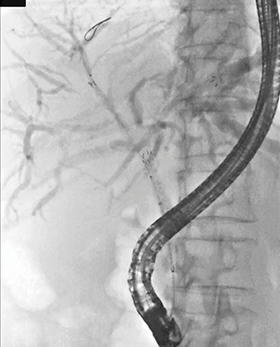

症例3は、卵巣がん術後の肝門部リンパ節転移症例である。肝門部の左側は完全に閉塞しており、左から右へとステントを進めた。メッシュの間隙をバルーンで拡張し、2本目のステント留置を行った(図10)。

図10 症例3:卵巣がん術後肝門部リンパ節転移(54歳、女性)

PSIS法による金属ステント留置

パルスレート7.5fps、線量モード:Normal